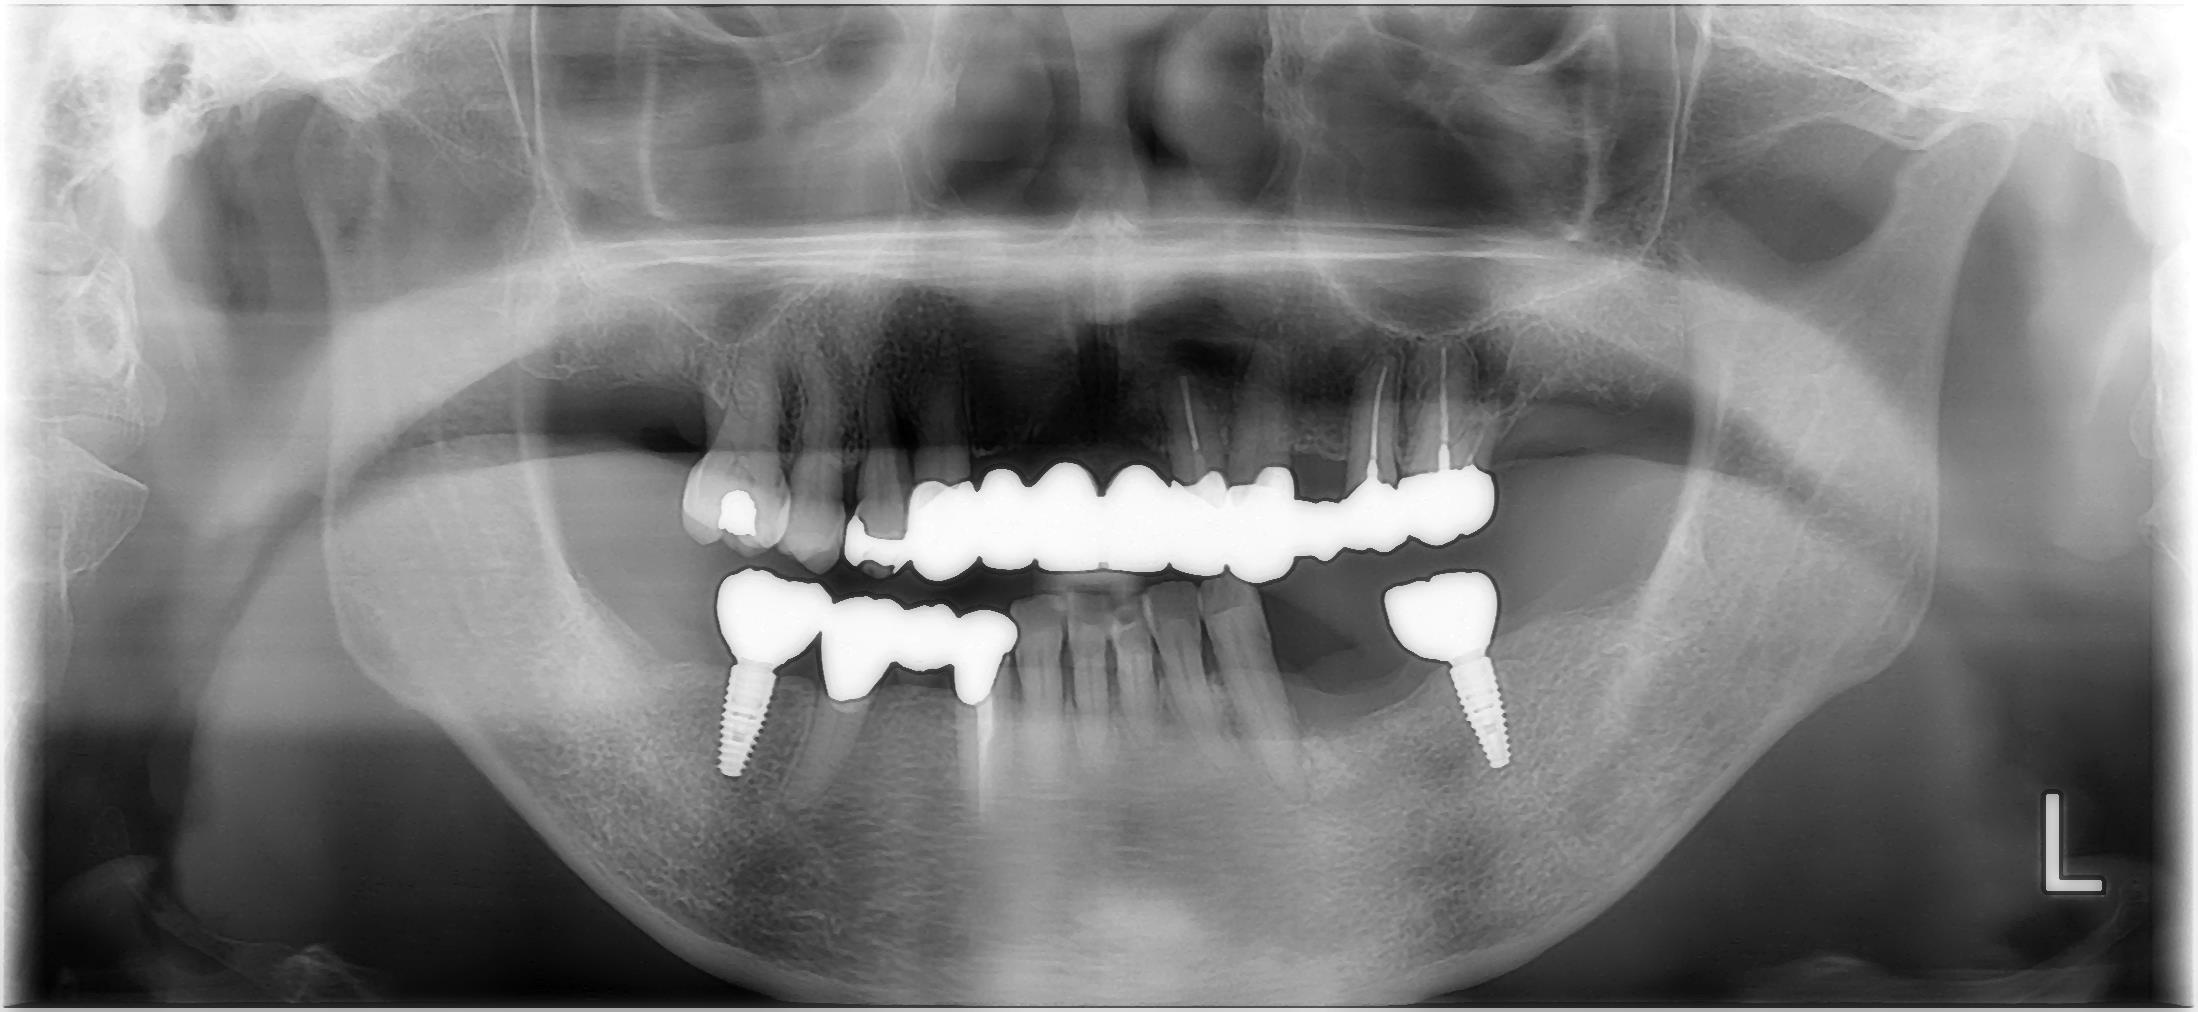

治療後

| 治療内容 | 抜歯 咬合挙上 セラミック治療 |

| 治療期間 | 6か月 |

| 費用 | セラミック治療485,100円(税込み) インプラント治療1409,650円(税込み) |

| 治療のリスク | 稀に割れることがあります。 |

| 所見 | 治癒に合わせて治療を行うため、仮歯の期間も長かったが、根気つよく真面目に通って頂けたおかげで安定した口腔内を確立できた。 |